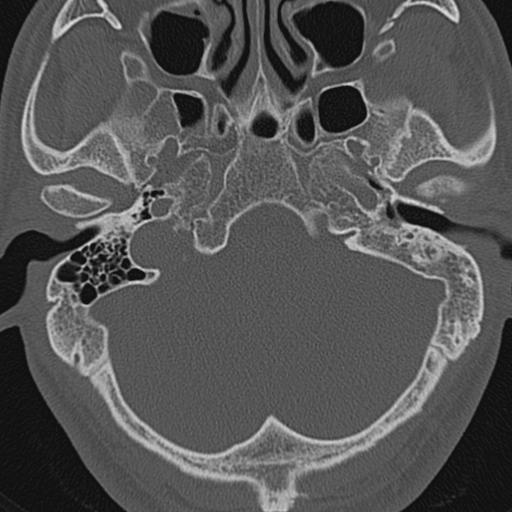

以下是引用zxl51642在2009-8-25 13:37:00的发言:[br]1、左侧慢性硬化型中耳乳突炎(中耳鼓室腔及听小骨受累),并胆脂瘤形成;2、左侧外耳道软组织密度影填塞,考虑炎性肉芽肿,建议结合临床;3、右侧颈静脉窝较左侧明显扩大,不排除颈静脉球瘤,建议mr进一步检查。

以下是引用随光逐影在2009-8-25 19:05:00的发言:[br]1)左侧慢性中耳乳突炎(肉芽肿或胆脂瘤形成),左侧外耳道炎性肉芽肿。2)右侧颈静脉球高位。